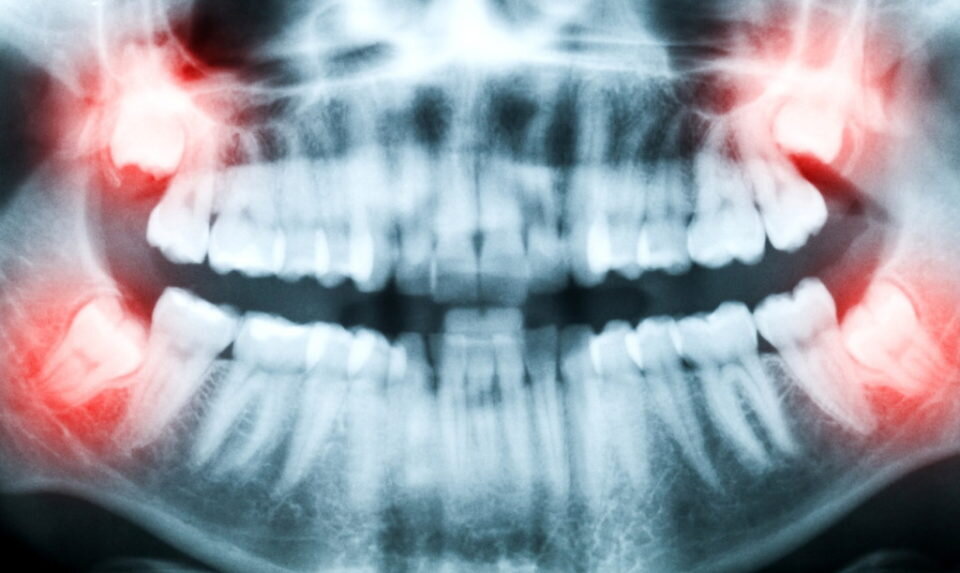

Начало прорезывания последних жевательных элементов происходит в 14-16 лет, у кого-то позже, в 20-28 лет. Все индивидуально. У одного и того же человека каждый элемент может давать о себе знать по-разному. И то, сколько зубов мудрости может вырасти над десной, тоже невозможно предположить. Например, по рентгенологическому снимку виден процесс их роста, но появятся ли они наверху над мягкой тканью в будущем неизвестно. События могут развернуться так, что во время прорезывания он появится лишь одной стороной или останется там полностью.

Определить сколько зубов мудрости вырастает у человека можно по диагностическому исследованию.

• Рентгенологическое челюстное исследование, на котором видно их расположение.

• А если сделать снимок 3D на томографе, будет заметно состояние корня и твердых тканей. Это поможет определить дальнейший прогноз.

При санации полости рта, не зависимо от того, сколько бывает зубов мудрости у человека на момент осмотра каждый стоматолог всегда уделяет им внимание у пациентов, возраст которых достиг 14 лет. Если уже начинает прорезываться один зуб мудрости сколько их, может быть потом, на визуальном осмотре определить нельзя. Для этого потребуется внутреннее исследование.

От их состояния и внутреннего расположения зависит возможность развития воспалительного процесса или разрушение соседних жевательных элементов.